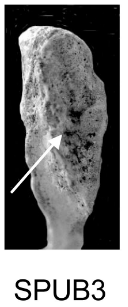

Demi-face antérieure (SPUB)

Changements morphologiques de la demi-face antérieure liés à la formation du rempart ventral.